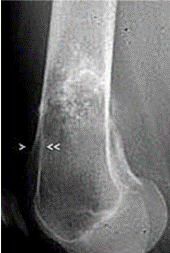

21

Q

Pathology?

A

Chondroblastoma

rare, benign neoplasm occurring second decade when growth plates are still open

70% in proximal humerus and knee, invariably at EPIPHYSIS

irregular but circumscribed, radiolucent epiphyseal lesion surrounded by reactive bone sclerosis